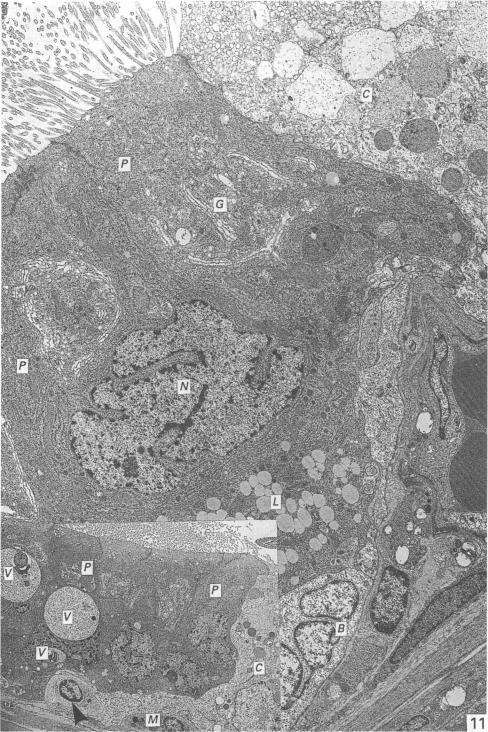

The ultrastructure of the epididymis of the African giant rat (Cricetomys gambianus, Waterhouse).

Oke B O, Aire T A, Adeyemo O, Heath E

J Anat. 1989 Aug;165:75-85.